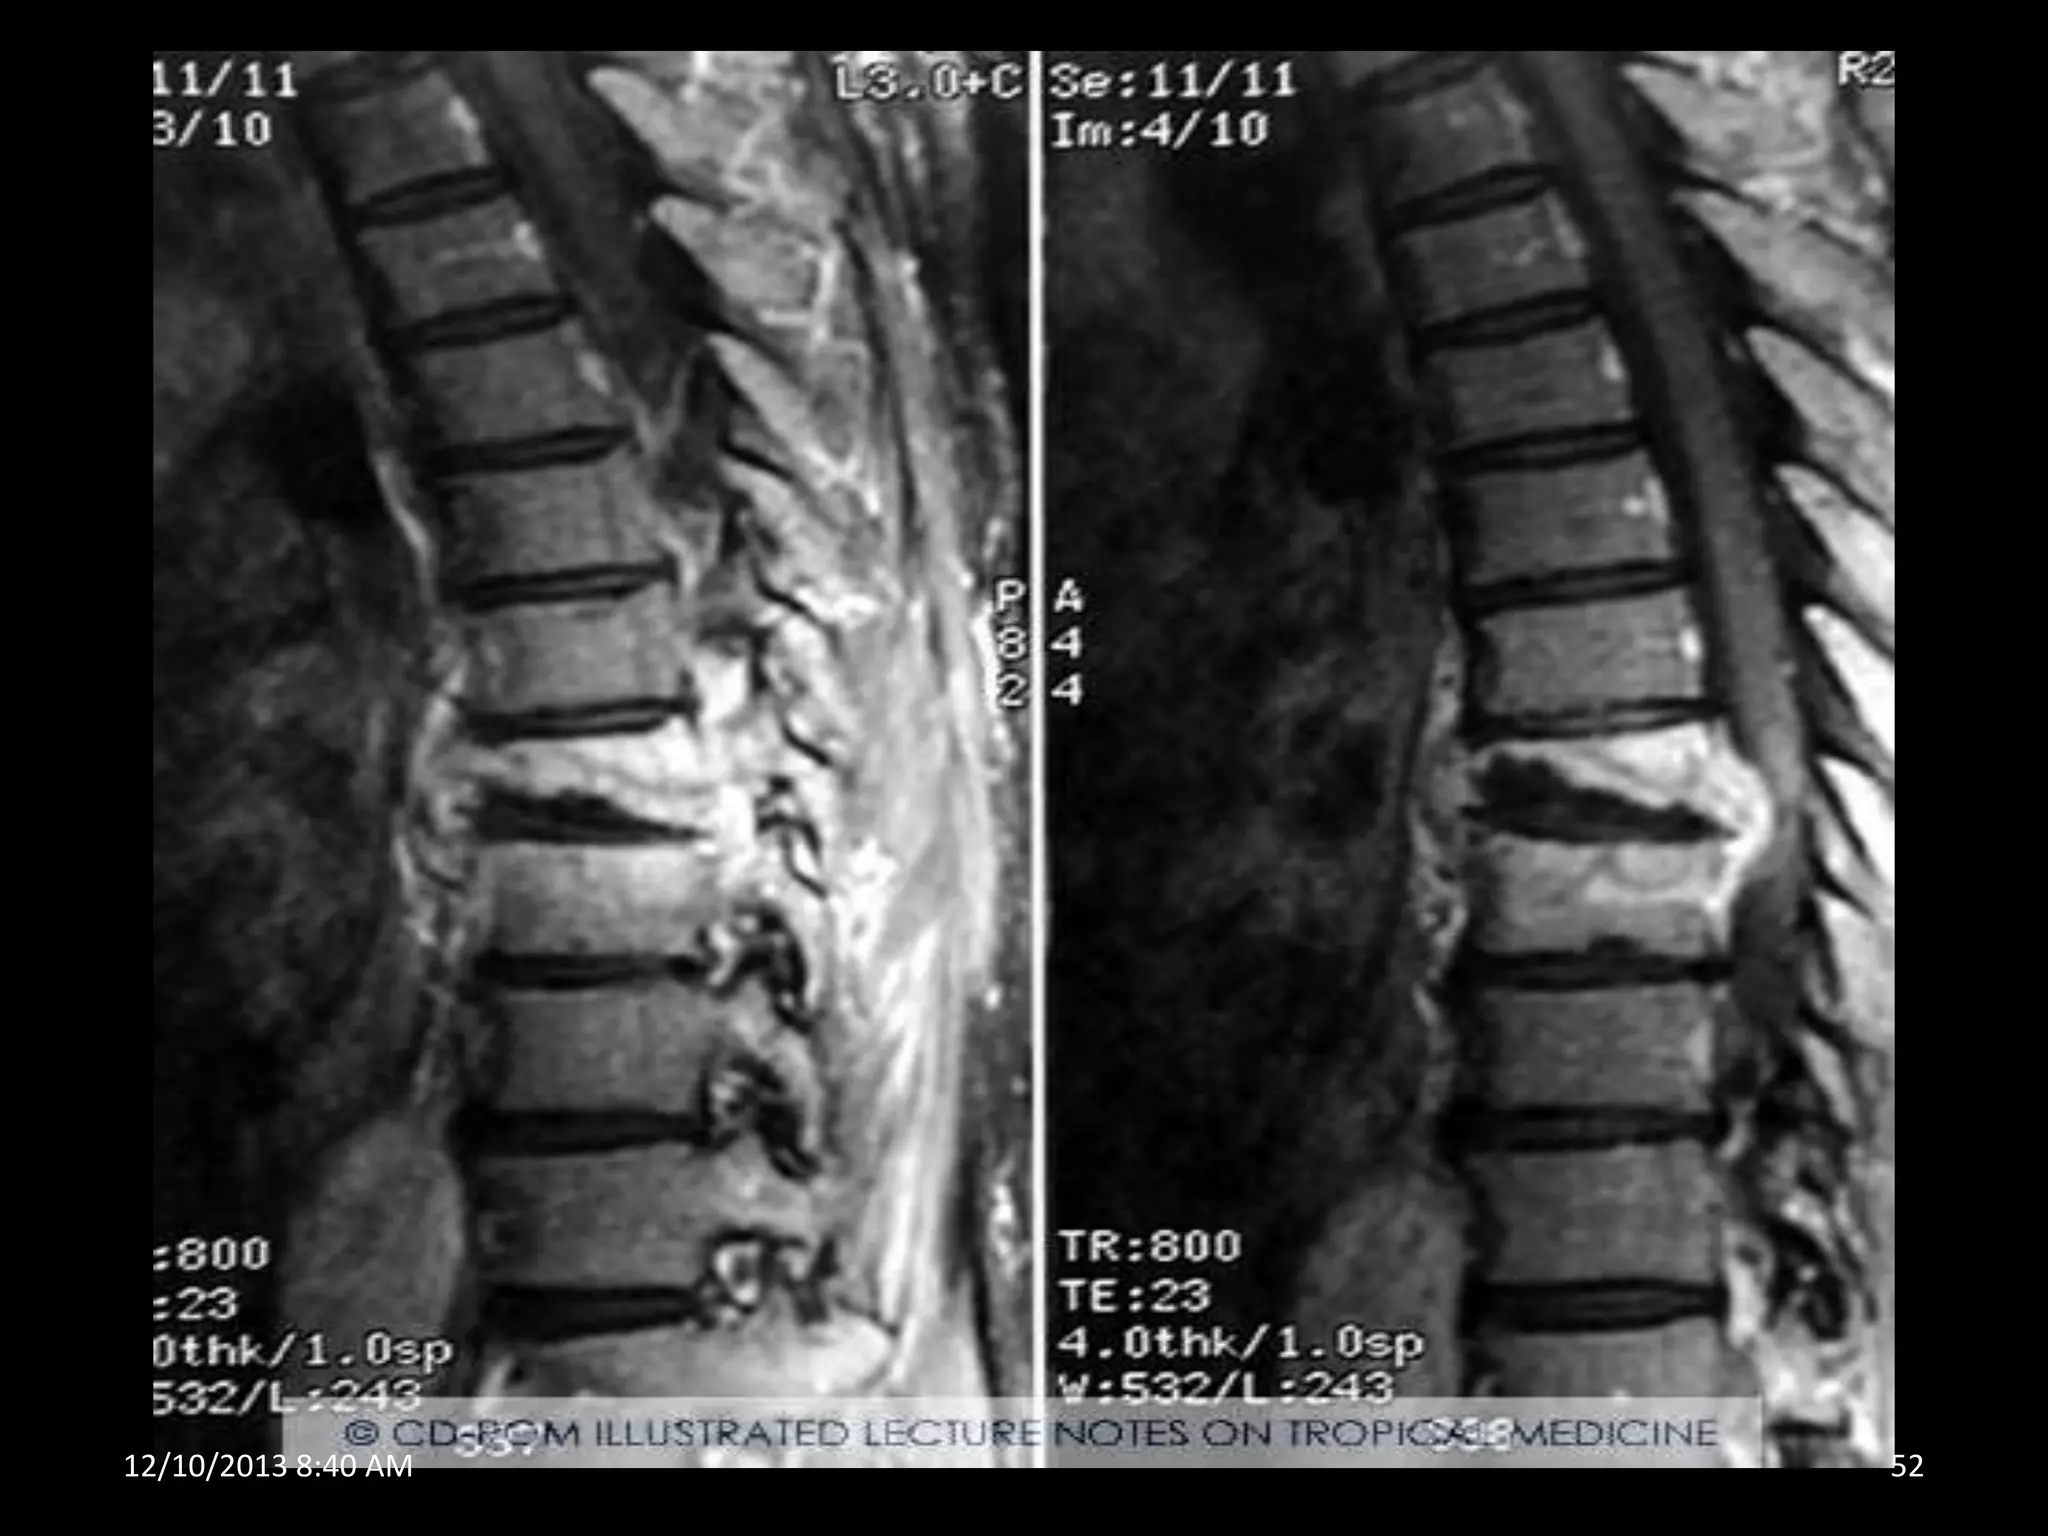

POTT`S DISEASE

THORACIC cord – most common

to adjacent bodies leading to their collapse and angulation of

spine

Conservative treatment with anti tuberculous chemotherapy

if severe- surgical decompression